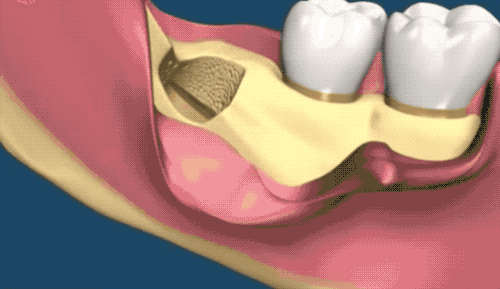

露出牙槽骨后,先削除一部分骨頭,露出躺臥如睡美人的橫阻生智齒...如果是已經(jīng)出肉的智齒,就沒(méi)這一步了。

請(qǐng)出那令人聞聲喪膽的牙科渦輪機(jī),先分割智齒,撬出塊頭過(guò)大的牙冠來(lái)...再把牙根磨切兩半,依次撬出來(lái)。當(dāng)然這樣的操作并不都是必須的,牙醫(yī)會(huì)依據(jù)當(dāng)時(shí)的可操作性去處理,畢竟每個(gè)哈姆雷特的橫阻生智齒也都可能長(zhǎng)得不一樣。

小編的智齒是還粘連了一部分肉,拔出來(lái)一些后,醫(yī)生又換手術(shù)刀把粘連的肉從智齒上切斷...牙醫(yī)操作的時(shí)候,總跟動(dòng)畫(huà)片主角放大招一樣,每次都要跟護(hù)士報(bào)工具名,刺激的小編真想要捂住嘴巴。